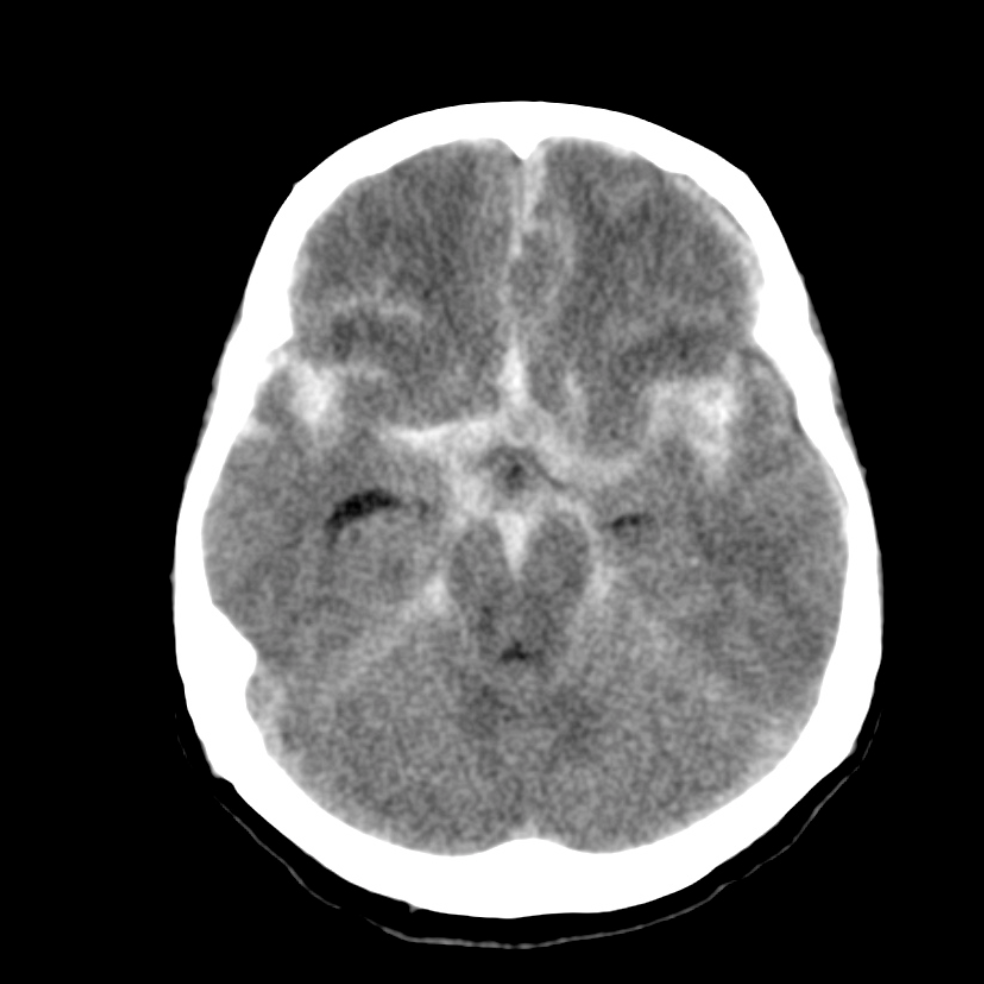

蜘蛛網膜下出血

出血位於蜘蛛網膜和軟腦膜之間,創傷、腦血管動脈瘤破裂是常見成因。患者會忽然覺得劇烈頭痛。治療上主要是控制血壓,減少腦水腫。